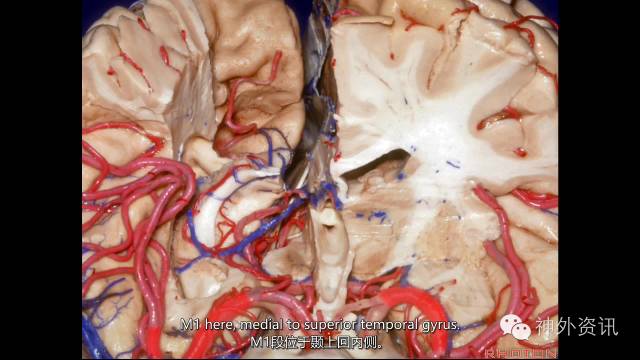

幕上主要血管

大脑前、中、后动脉。